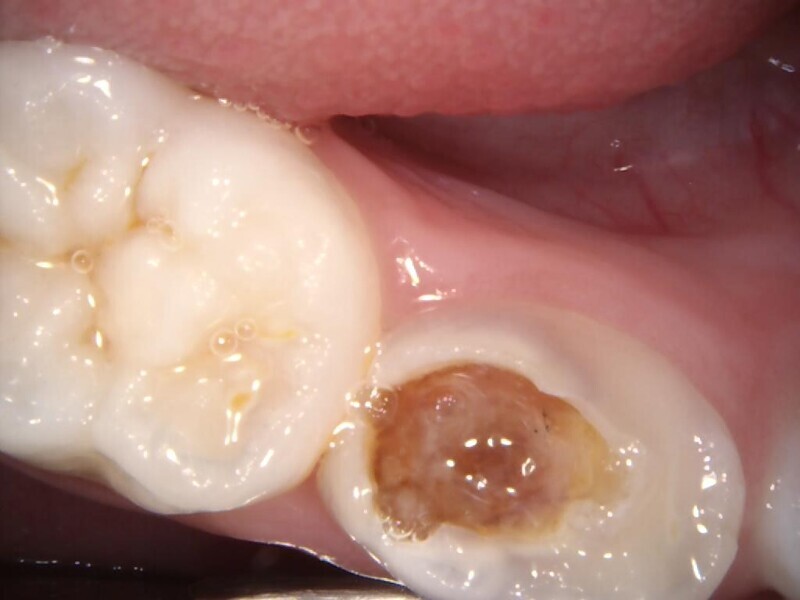

Cas 4 (Figs. 14 à 18)

Ce patient âgé de 4 ans et 6 mois présentait une douleur constante qui était apparue spontanément au niveau de la première molaire temporaire inférieure gauche, et persistait depuis plusieurs jours. Toutefois, aucun œdème facial ou gonflement du versant vestibulaire de la gencive n’était visible. Des caries profondes étaient présentes, mais il n’y avait ni mobilité dentaire ni profondeur de poche importante au sondage. La radiographie montrait un risque d’effraction de la cavité pulpaire lié à la lésion carieuse, et une atteinte de la zone de furcation correspondant à un défaut osseux. Une pulpectomie était le traitement de choix. L’élimination de la lésion carieuse a entraîné une exposition de la pulpe, mais aucun saignement n’a été observé. Une nécrose pulpaire a été diagnostiquée. Quatre canaux, deux mésiaux et deux distaux, ont été localisés et la dent a été obturée. Lors du second rendez-vous, la dent était asymptomatique et elle a été restaurée au moyen d’une couronne en acier inoxydable. À la visite de suivi à 30 mois, la dent ne présentait aucun symptôme et la radiographie a montré un processus éruptif normal.